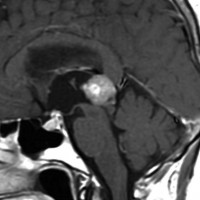

14歳の男の子です。このMRI画像はどう見ても松果体奇形腫 mature or immature teratoma 以外には考えられません。左の写真で脂肪腫が混じっていることが解ります。AFP 130 ng/ml, HCG-beta 30 mIUでしたから,ICE化学療法と放射線治療 (全脳室 25.2グレイ/15分割と局所28.8グレイ,1回線量1.8グレイ)をして少し小さくして(右の写真)から開頭手術しました。全摘出して病理診断は成熟奇形腫でしたが,治療前にはおそらくもっと未熟な部分が混じっていたと考えられます。